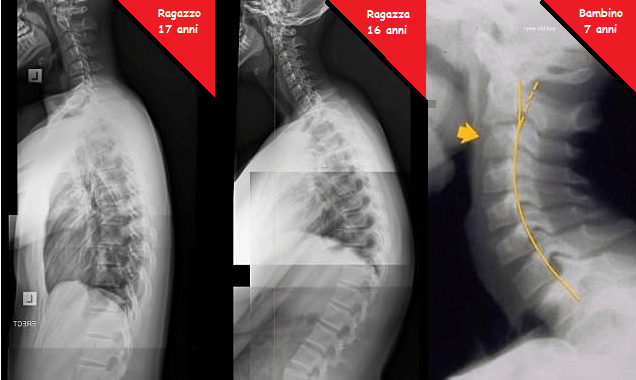

Il dottor James Carter, un famoso chiropratico australiano, di Niagara Park nella Nsw Central Coast, ha pubblicato sul Daily Mail Australia le lastre di alcuni bambini di 7 anni nelle quali si vedono i danni causati dall’uso eccessivo di Smartphone e Tablet alla loro spina dorsale.

Tale condizione chiamata “text neck” (letteralmente collo da testo) è, purtroppo, comune a molti bambini e adolescenti, come testimonia il dottor Carter il quale dichiara di aver visto un notevole aumento di questi disturbi negli ultimi anni. «Ho iniziato a vedere molti casi di questo tipo negli ultimi due anni, specialmente in bambini e adolescenti che trascorrono troppe ore con la testa china a scrivere sms. Tali ragazzi sembrano avere una schiena a ‘zainetto’, che spesso fa male o provoca dolore a testa, collo e spalle nonché intorpidimento e dolore a mano e braccia e, addirittura, ansia».

Da quanto sostenuto dallo specialista sembra che il 50% delle persone affette da tale disturbo, il Test Neck, sono adolescenti in età scolare. I ragazzi, così come dimostrano le radiografie, si ritrovano con la schiena curva e seri problemi di postura.

Ecco quindi spiegate le foto shock che dimostrano quanto sostenuto dal dottor James Carter e avvalorato anche da un altro dottore, Kenneth Hansraj, il quale spiega che il peso sul collo aumenta quando la testa si curva in giù, postura utilizzata quando si utilizzano Smartphone e Tablet.